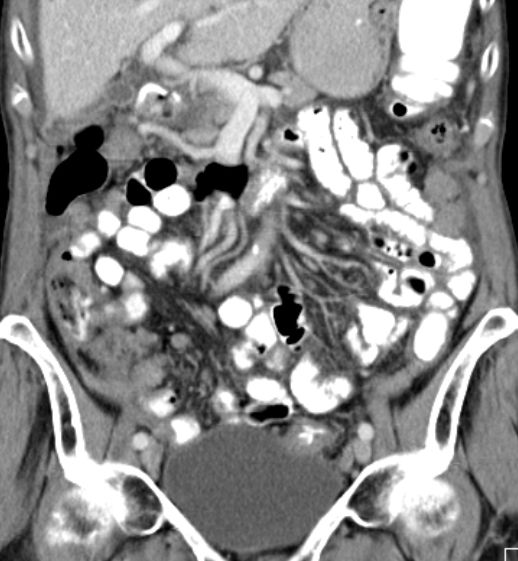

Ascites bei Ovarial - Ca |

Pleuraerguß links bei Ovarial - Ca |

Fortgeschrittenes Ovarialkarzinom mit Ascites und Peritonealkarzinose.![]() | ||